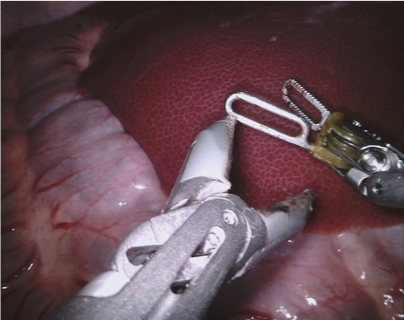

In 2017 we organized a follow-up challenge222https://endovissub2017-roboticinstrumentsegmentation.grand-challenge.org where a team at Intuitive Surgical manually segmented images from porcine robot assisted nephrectomy procedures. We aimed to improve on the previous challenge by first increasing the label quality by using hand-created labels rather than automatic labelling, secondly by adding greater variance in the background by using 10 separate procedures and finally by providing more type and part labels for the instruments.

We provided the first 225 frames of 8 sequences as training data and kept the last 75 frames of those 8 sequences as test data. 2 of the full 300 frame sequences were kept as test sequences. Test labels were kept hidden from the participants. Our datasets contain 7 different robotic surgical instruments. The Large Needle Driver, Prograsp Forceps, Monopolar Curved Scissors, Cadiere Forceps, Bipolar Forceps, Vessel Sealer and additionally a drop-in ultrasound probe, which is typically held in the jaws of the Prograsp Forceps instrument. Samples from the training datasets are depicted in Fig. 2 and examples of the different instrument types are shown in Figure 3 and 4.